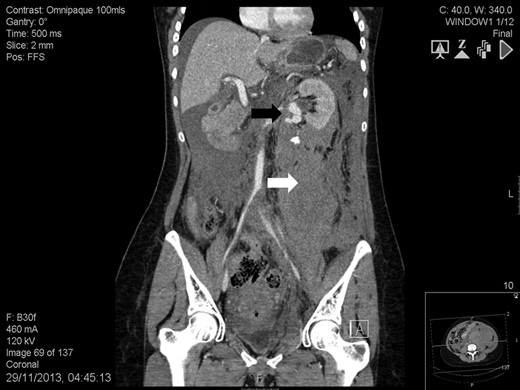

A 41-year-old woman, 21-week pregnant, presented to the Emergency Department with left-flank pain, hypotension (100/60 mmHg) and tachycardia (95 bpm). Blood tests were: haemoglobin 7.3 g/dL, leukocytosis 23.4 cell × 109/L, lactate 3.6 mmol/L, base excess −8.4 mol/L and serum creatinine 82 mmol/L. Abdominal ultrasound was normal but foetal monitoring demonstrated a drop in heart rate suggestive for impending demise. Placental abruption was suspected and following resuscitation she was brought to theatre. We found a large left-sided retroperitoneal haematoma and a non-viable foetus. Exploration also revealed a ruptured left RAA and a contralateral RAA. At this point, it was felt a percutaneous approach would have been more appropriate. Contrast-enhanced computed tomography showed a massive retroperitoneal haematoma, a ruptured left RAA (Fig. 1), and an intact right-sided RAA measuring 2.2 cm (Fig. 2). Under selective angiography, the aneurysm was embolized and the bleeding controlled [3]. Recovery was rapid but a DMSA scan performed 2 weeks later, demonstrated reduced function in the treated kidney (37%). The risk of rupture of the right RAA was deemed significant and a plan for repair was made. The lesion was saccular, wide-necked and located at the artery bifurcation thus preventing endovascular treatment. We opted for hand-assisted retroperitoneoscopic nephrectomy, ex-vivo repair and autotransplant.

Abdomen contrast-enhanced computed tomography scan: massive retroperitoneal haematoma (white arrow) with active bleeding from a ruptured 2-cm left renal artery aneurysm (black arrow).